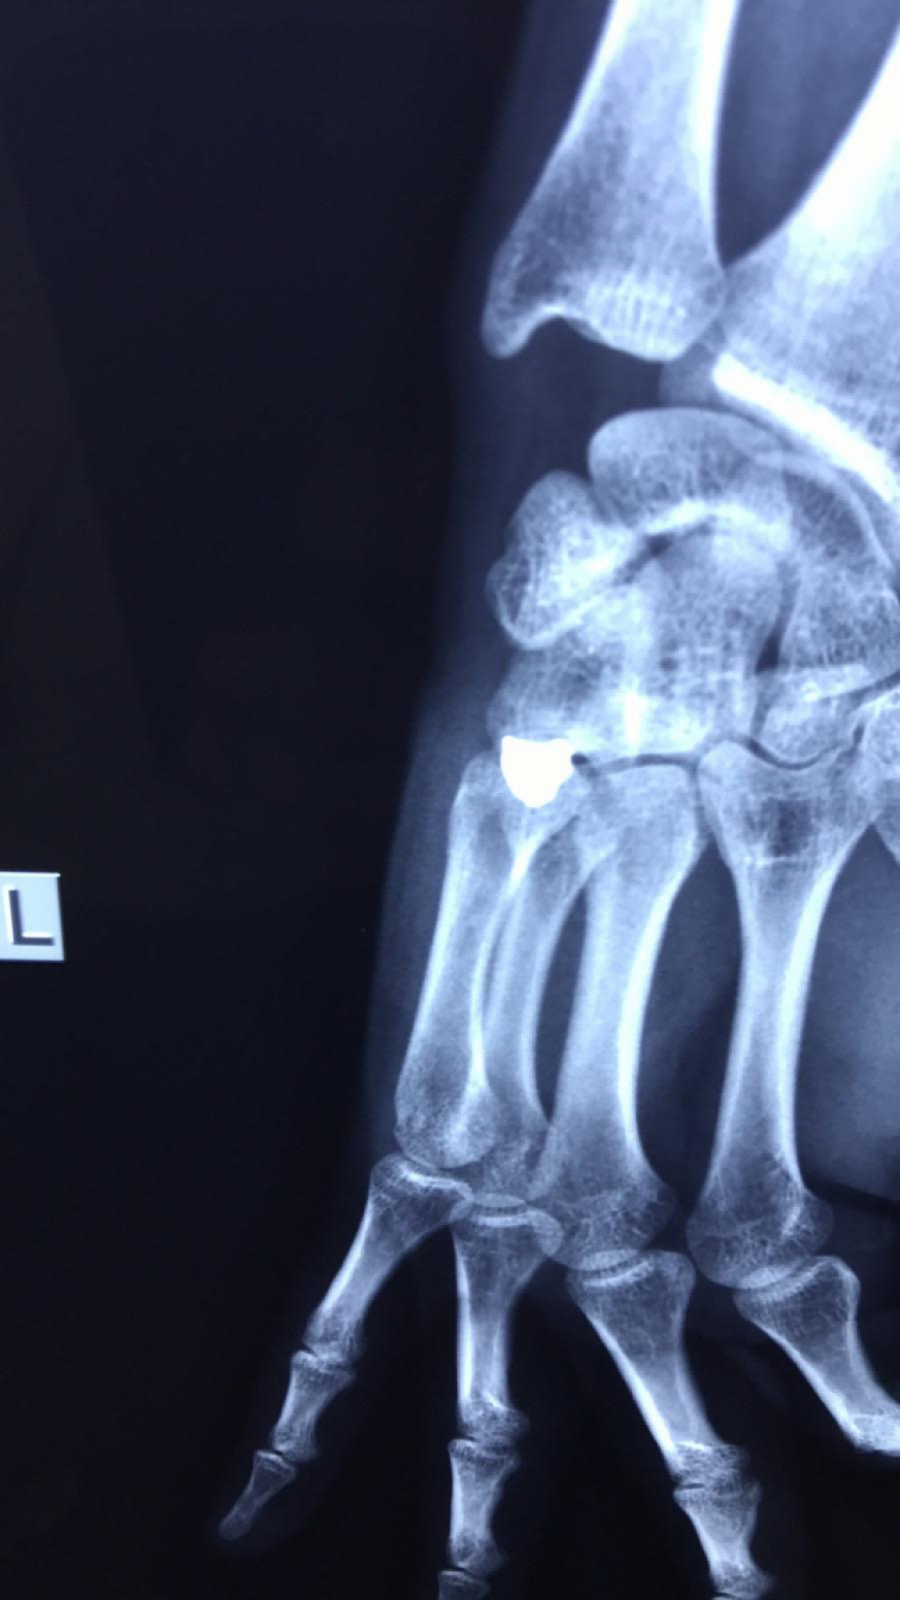

OBJAVLJEN RENDGENSKI SNIMAK Ovo je metak koji je izvađen iz šake srpskog mladića (FOTO)

U KBC Gračanica Miloš S. (21) izvađen metak koji je bio u šaci.

Ovde možete pogledati i rendgenske sinimke šake ranjenog mladića.